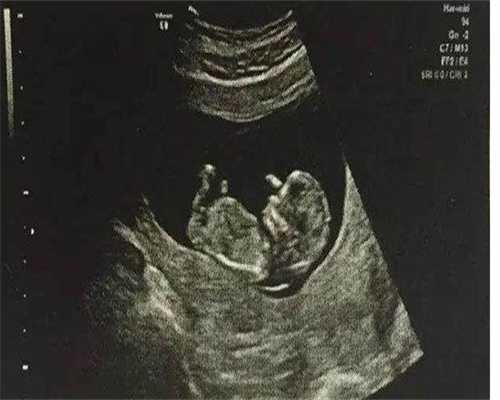

1、第三代试管培育后,医师会对胚胎进行检测,意图是在移植时尽或许防止染色体反常的胚胎,一起在这个历程中也能够进行性别筛查。